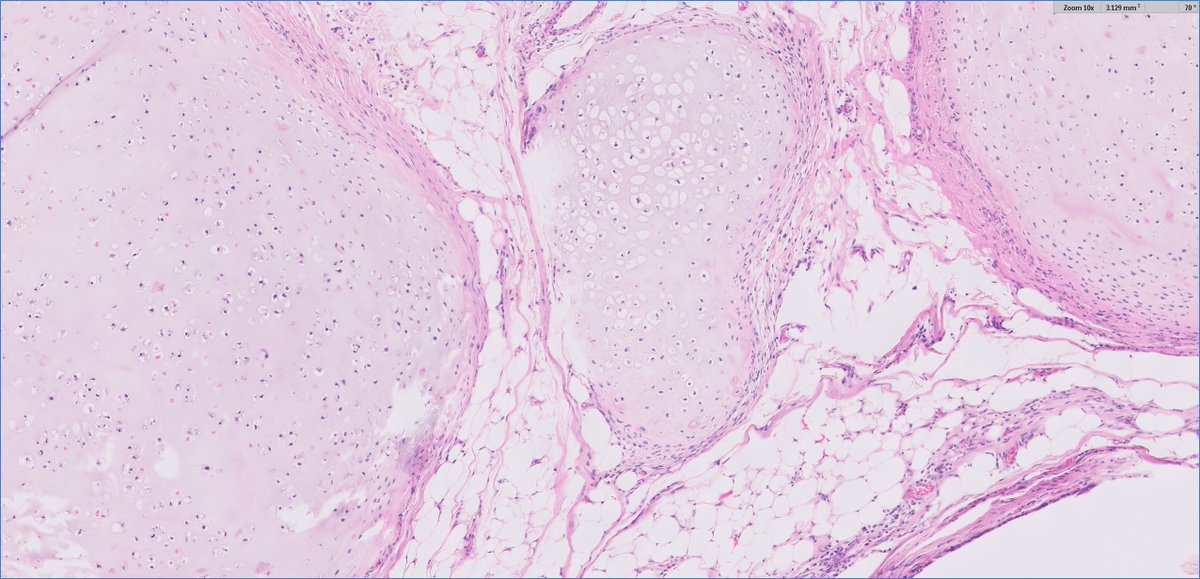

#GUpath orchiectomy for mixed GCT, rep sections shown here stage based on these 2 pics? ⏬poll to follow⏬